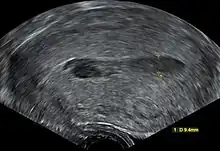

| Transvaginal ultrasonography of a hematometra after childbirth, seen as a hypoechoic (darker) area within the uterine cavity. The cervix is located to the left in the image, and the fundus is located to the right. | |

Although hematometra can often be diagnosed based purely on the patient's history of amenorrhea and cyclic abdominal pain, as well as a palpable pelvic mass on examination, the diagnosis can be confirmed by ultrasound, which will show blood pooled in the uterus and an enlargement of the uterine cavity.[4][5] A pyelogram or laparoscopy may assist in diagnosing any congenital disorder that is suspected to be the underlying cause of the hematometra.[2]